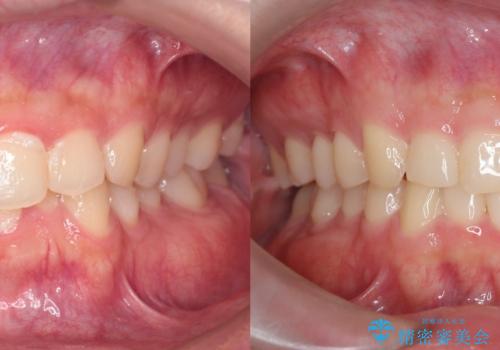

- 患者様は、全体的な歯列のガタガタとディープバイト(深い噛み合わせ)を主訴として来院されました。診断の結果、ディープバイトを改善するためには、歯列全体の拡大が必要であると判断しました。治療には、透明なマウスピース型矯正装置「インビザライン」を使用し、歯を適切に拡大しながら歯並びを整える計画を立てました。治療期間はおおよそ2年を見込んで進め、最終的に見た目にも大きく変化をもたらすことを目指しました。

ディープバイトの治療には、奥歯の高さや前歯の位置に対する繊細な調整が必要です。本症例では、インビザラインによる歯列拡大を行うことで、噛み合わせを改善し、歯並び全体を整えました。治療過程では、歯間のスペースを確保するため、IPR(インタープロキシマルリダクション)を適宜行い、無理なく歯列の調整を行いました。治療後は、歯並びが大きく改善され、患者様の見た目にも大きな変化が現れました。インビザラインは透明で目立たず、治療中の見た目を気にされる患者様にも配慮した治療法です。